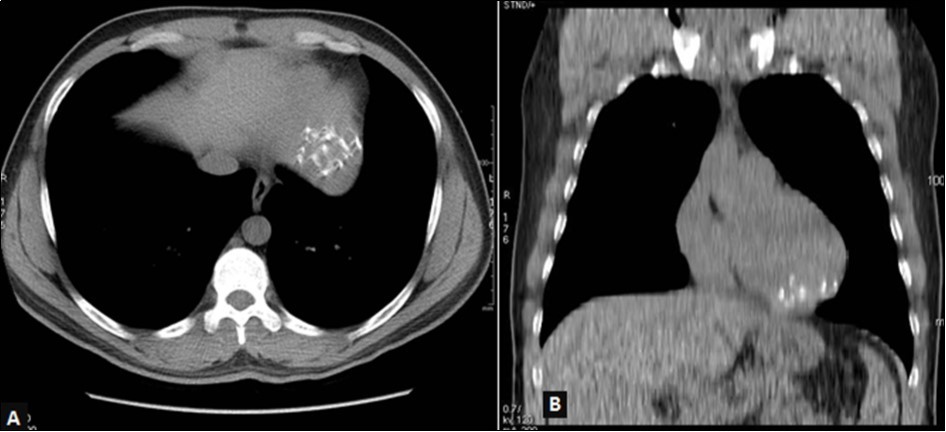

The 64-slice computed tomography (CT) showed a left ventricle intra-myocardial mass of tissue density (25 HU), not enhancing after injection of contrast, and containing multiple central and peripheral arciform calcifications (Figure 3,Figure 4,and Figure 5).

Figure 3.Thoracic CT without injection, mediastinal window, axial view (A) and coronal reconstruction (B): left ventricular mass with multiple calcifications in strata.